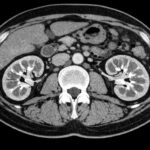

Στένωση ουρητήρα (συγγενής ή επίκτητη)